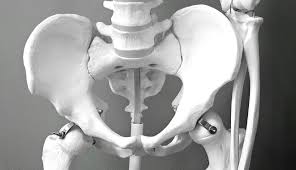

1. 고관절의 위치와 역할 ⚙️

고관절은 허벅지뼈(대퇴골)와 골반뼈(비구)가 만나는 부분으로, 걷기, 앉기, 달리기 등 대부분의 하체 움직임을 담당합니다.

공처럼 생긴 대퇴골 머리가 관절 안에 들어가 회전하면서 부드러운 움직임을 가능하게 합니다. 하지만 이 부위는 체중을 많이 받기 때문에 쉽게 손상될 수 있습니다.